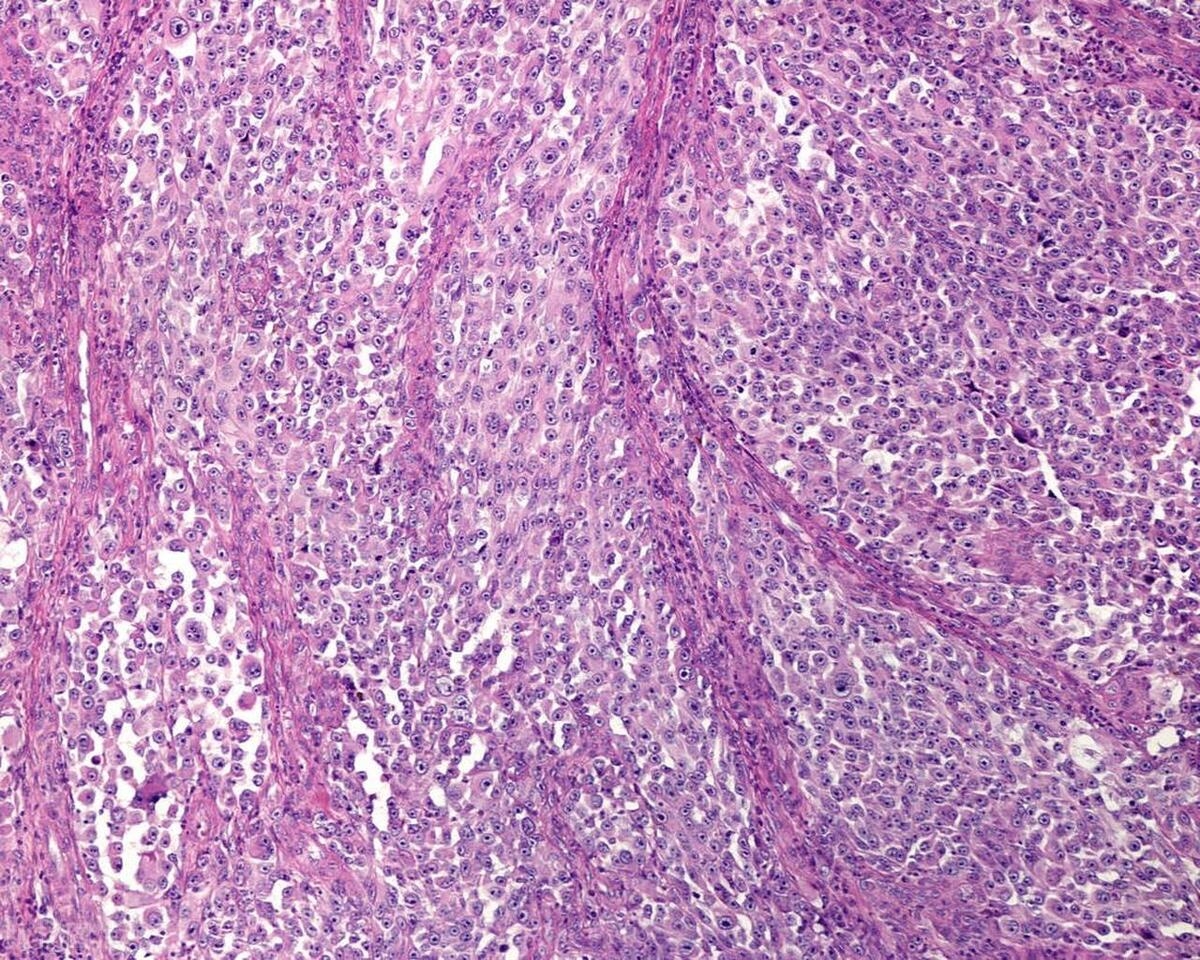

和老張的妻子聊過後,醫生對老張的雞眼產生了濃厚的興趣,於是將老張左腳的止血棉扯了下來,沒想到他們看到的是一顆增大了不少的「雞眼」,醫生看到后連拍大腿:「哎喲,這哪裡是雞眼啊,這分明是黑色素瘤啊」。

經過病理組織分析,老張患的就是黑色素瘤,而且已經到了晚期階段,無法進行手術和治療。在醫生的解釋下,妻子了解了這種病,知道老公如今沒救了,最終選擇帶著老張回到了老家。

什麼是黑色素瘤?

黑色素瘤是一種惡性腫瘤,在我國的發病率為百萬分之八,但是在發達國家,這種疾病的發病率最高可以達到十萬分之五,是中國黑色素瘤發病率的十幾倍。

不過黑色素瘤的死亡率比較低,治療后五年死亡率2%,但是不治療的話存活率只有5%,因此早期治療黑色素瘤還是很重要的。